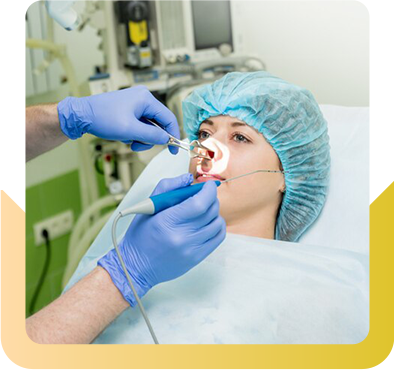

Consultation

Redefine Your Confidence with Expert Rhinoplasty Consultation Services!

Enhance your confidence with professional rhinoplasty consultation services. Our expert team offers personalized advice, helping you achieve your desired nose shape and boost self-assurance through tailored solutions and careful, experienced guidance every step of the way.

How to Prepare for Rhinoplasty

- Medical History Review – Discuss reasons for surgery (cosmetic or functional), overall health, past nasal issues, previous surgeries, and medications.

- Physical Examination – The surgeon assesses facial structure, nasal interior, and breathing function, especially for conditions like a deviated septum.

- Photographs – Pre-surgery photos are taken from multiple angles for before-and-after documentation.

- Discussion of Expectations – Have an open conversation about goals, realistic outcomes, and any concerns about appearance or breathing. Proper discussions and assessments ensure you are well-prepared and that expectations align with surgical possibilities.